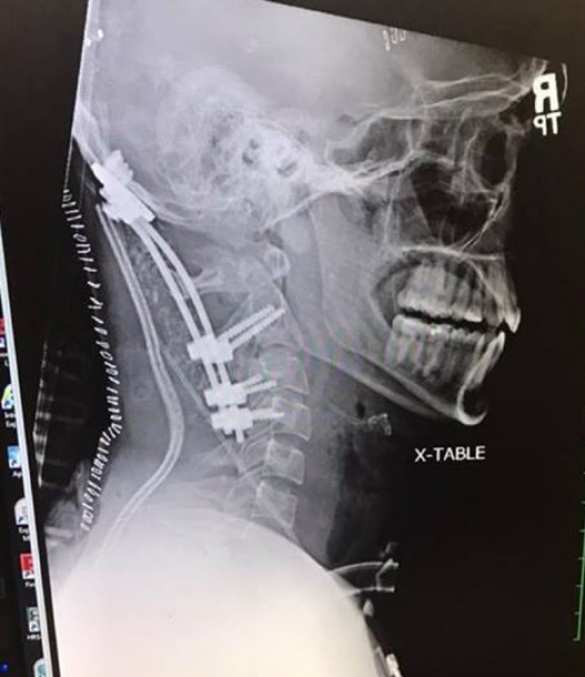

Невероятный инцидент с сохранением у пострадавшего всех жизненных функций после так называемого «внутреннего обезглавливания» (когда череп полностью отделяется от позвоночника, и голова держится лишь на коже, сосудах и нервных пучках) поразил и медиков.

Врачи диагностировали у него атланто-затылочную дислокацию — то самое «внутреннее обезглавливание». Практически во всех известных случаях она оказывалась смертельной.

Хирурги провели сложнейшую операцию, закрепив в шее мужчины металлические штифты, которая оказалась успешной.